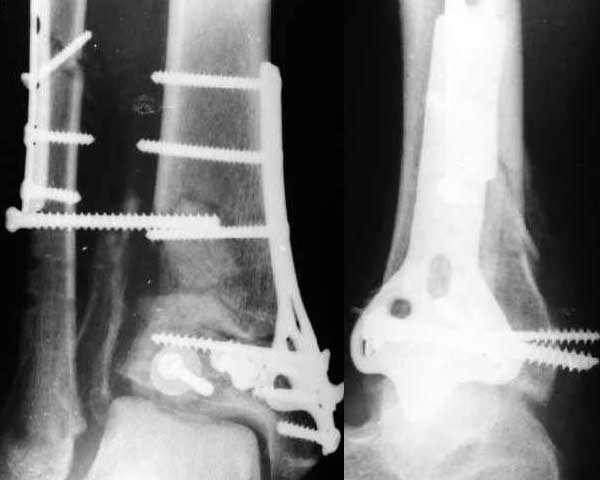

Отправитель: Alexander Chelnokov 07 Август 2003, 12:54

> 1. Whould be interesting to see pre-op X ray.

Attached.

Кликните для загрузки файла get_image.jpg

30KB (30760 bytes)